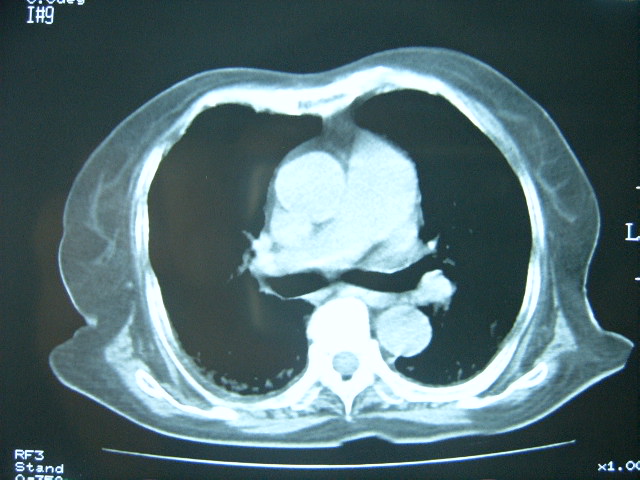

标题: CT7574:双肺病变,请会诊。急!急!

女 79岁,今日高烧,无咳嗽及痰,是否粟粒结核还是?

双肺弥漫小结节状高密度,部分融合,边界不清(因为不是hrct,可能为部分容积效应引起),肺门纵隔内未见肿大淋巴结影。无胸腔积液。

考虑:急性血型播散型肺结核,不除外过敏性肺炎;建议治疗后复查。

双肺弥漫性结节影,双肺上叶为著.纵隔内可见一肿大淋巴结影,密度较高.支持急性血行播散型肺结核.双侧少量胸腔积液.

双肺弥漫基本均匀分布的小结节状高密度影,部分融合。支持急性血性播散性肺结核。

两肺弥漫分布小结节状高密度影,其大小,密度一致,分布均匀,并可见与后胸壁平行的弧状影

诊断:两肺急性血型播散形肺结核

两肺下叶见高密度钙化灶,支持急性血型播散型肺结核。